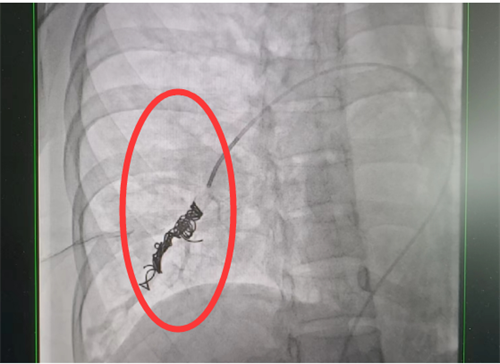

目前治疗肺动静脉瘘的方法有两种—介入手术及外科切除,可根据患者具体情况选择合适干预方式。通过积极处理,梁瑶脑梗症状得到控制,随后转入香港马会app外周血管介入科进行介入手术治疗。此类手术难度大,风险高,经科室团队仔细讨论,定下最佳方案,为患者顺利实施了肺动静脉瘘封堵术,手术全程4小时,术后平稳回到病房。术后复查肺动静脉瘘已消失不见,经过后续的对症治疗和护理,梁瑶恢复良好,于5月上旬出院。

栓塞术后造影